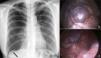

A 41-year-old woman with a history of spontaneous right pneumothorax, treated with thoracic drainage, was evaluated in our department for a relapse of the same condition. Chest X-ray revealed, in addition to pneumothorax, diaphragmatic lobulation (Fig. 1a, arrow). Video-assisted thoracoscopy revealed congenital diaphragmatic hernia (Fig. 1b), which was repaired with separate monofilament sutures. No other lesions were identified that could explain the origin of the pneumothorax (Fig. 1c). The patient was discharged on day 4 after surgery, with no complications.1

Fig. 1.

(a) Posterolateral chest X-ray showing complete right pneumothorax with no mediastinal shift. Diaphragmatic lobulation is also seen (arrow). (b) Right diaphragmatic herniation on video-assisted thoracoscopy, showing the hepatic dome. (c) Herniation closed by separate monofilament sutures.